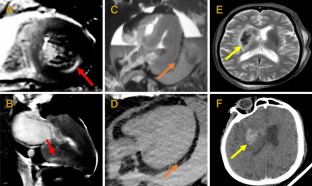

Conventional autopsy is the gold standard for identifying unexplained death but due to declines in referrals, there is an emerging role for post-mortem imaging. We evaluated whether post-mortem magnetic resonance (PMMR) and computed tomography (PMCT) are inferior to conventional autopsy. Deceased individuals ≥ 2 years old with unexplained death referred for coronial investigation between October 2014 to December 2016 underwent PMCT and PMMR prior to conventional autopsy. Images were reported separately and then compared to the autopsy findings by independent and blinded investigators. Outcomes included the accuracy of imaging modalities to identify an organ system cause of death and other significant abnormalities. Sixty-nine individuals underwent post-mortem scanning and autopsy (50 males; 73%) with a median age of 61 years (IQR 50–73) and median time from death to imaging of 2 days (IQR 2–3). With autopsy, 48 (70%) had an organ system cause of death and were included in assessing primary outcome while the remaining 21 (30%) were only included in assessing secondary outcome; 12 (17%) had a non-structural cause and 9 (13%) had no identifiable cause. PMMR and PMCT identified the cause of death in 58% (28/48) of cases; 50% (24/48) for PMMR and 35% (17/48) for PMCT. The sensitivity and specificity were 57% and 57% for PMMR and 38% and 73% for PMCT. Both PMMR and PMCT identified 61% (57/94) of other significant abnormalities. Post-mortem imaging is inferior to autopsy but when reported by experienced clinicians, PMMR provides important information for cardiac and neurological deaths while PMCT is beneficial for neurological, traumatic and gastrointestinal deaths.